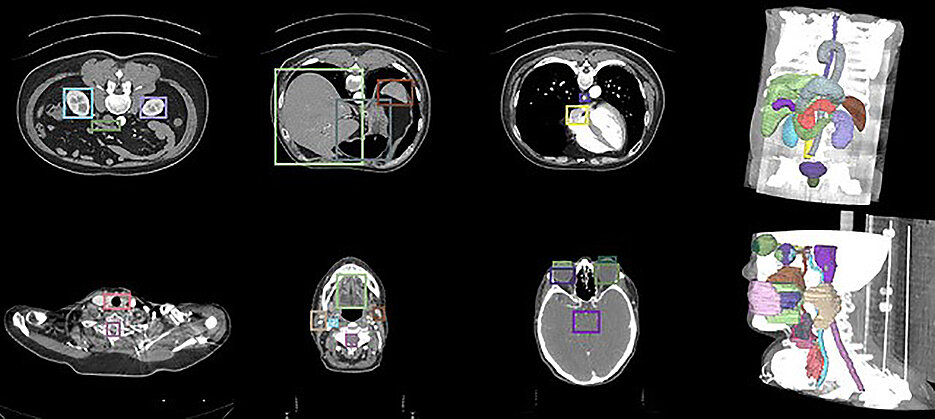

„Unser Team hat ein KI-Modell entwickelt, das dreidimensionale medizinische Bilddaten, etwa aus CT-, MRT- oder Ultraschalluntersuchungen, nicht nur automatisch segmentiert, sondern auch interaktiv verfeinern kann“, erklärt der Informatiker. „Segmentierung“ bedeutet in diesem Fall, dass die KI ein Bild in verschiedene Bereiche unterteilt und, wenn gewünscht, bestimmte Strukturen gezielt identifiziert und hervorhebt – also beispielsweise Lungengewebe rot darstellt und einen kleinen Tumor gelb hervorhebt.

Die „interaktive Verfeinerung“ setzt auf die Unterstützung durch die Anwenderinnen und Anwender. „Diese können beispielsweise mit einfachen Klicks eine Region markieren, die das Modell übersehen hat. Das System reagiert darauf in Echtzeit und passt die Segmentierung entsprechend an“, erklärt Krenzer. Dabei handele es sich um eine Art „Dialog zwischen Mensch und KI“.

Technisch basiert das neuentwickelte KI-Modell auf einer besonders schnellen und speichereffizienten Variante bereits existierender Modelle, die ursprünglich für die Analyse von Videos entwickelt wurden. „Wir haben diese Architektur für den medizinischen Bereich angepasst und um Mechanismen erweitert, die eine konsistente Segmentierung über mehrere Bildschnitte hinweg ermöglichen“, so Krenzer. Aufgrund seiner technischen Spezifikationen kann das Modell anatomische Strukturen über die Tiefe des Volumens hinweg erkennen, stabil verfolgen und gezielt verbessern.